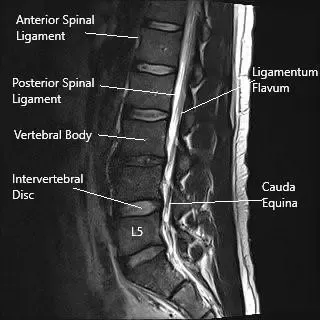

Imagen de resonancia magnética en sección sagital mostrando la columna lumbar.